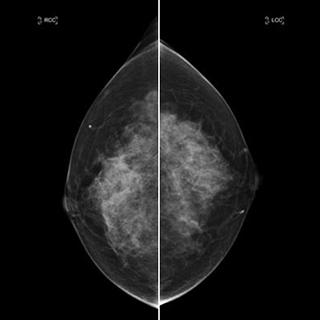

乳腺撮影

エックス線を用いた乳房撮影をマンモグラフィといいます。乳房の大部分は、乳腺を脂肪組織で構成されており、普通のエックス線検査で使用される装置では診断に有用な画像を得ることができません。マンモグラフィによって、視触診では分からない早期乳がんの発見が可能となります。

乳房は丸みを帯びているため、プラスチック板とフィルム支持台で乳房を挟み、均等な厚みにすることで乳腺の重なりを減らし、病変部の描出能を向上させ、少ないエックス線量で撮影することが可能となります。原則として2方向で撮影します。また撮影乳房は、症状がある側(検測)だけでなく、症状がない対側乳房も撮影します。通常のレントゲン撮影と異なり、軟エックス線を用いて撮影するため、髪の毛や薄い衣服なども障害陰影となるため、当院では基本的に上半身は裸の状態で撮影します。撮影時に髪が写り込む可能性がある時は髪をまとめていただくことがあります。また清涼パウダーボディー用ファンデーションなどはマンモグラフィでは障害陰影となる場合がありますので、ご使用をお控えください。検査において乳房の厚みを均一にして固定するため、痛みを伴う場合があり、全く痛みを感じない方、強く痛みを感じる方、人それぞれです。

乳房をそのままの厚みで撮影した場合、乳腺・血管・脂肪などの重なりで、病気があったとしても写真には写りません。乳房の病気には、0.1mm程度のとても小さな病変だけが早期発見の手掛かりになることもあり、そのため乳腺を広げて固定して、できるだけ乳房を薄く広げて撮影しなければ良い写真を撮ることはできません。我慢できるぎりぎりまで乳房を圧迫することは大変重要なことです。(圧迫板は一定以上の圧力がかからないよう設計してあります)ご協力お願いします。

基本の2つの撮影方向

• 内外斜位方向撮影(MLO)

• 頭尾方向撮影(CC)

その他、精密検査での拡大撮影や乳管造影検査などがあります。